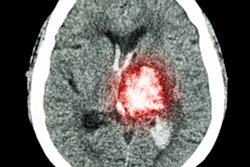

Trained using 414 patients clinically diagnosed with Alzheimer's disease and normal controls in the ADNI, the researchers' fully convolutional neural network (CNN) generates color-coded disease probability maps after analyzing T1-weighted brain MR images. Next, a multilayer perceptron analyzes these disease probability maps to produce a binary classification of Alzheimer's disease status.

In other results, the model's identification of high-risk cerebral regions closely tracked postmortem histopathological findings, according to the researchers.